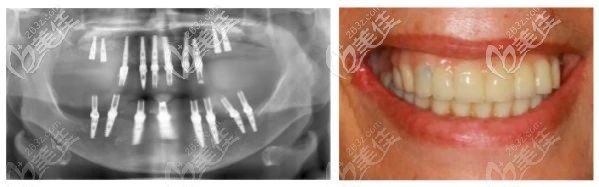

術(shù)后照片:

為了幫助老人實(shí)現(xiàn)即刻負(fù)重,在下頜拔牙后使用去骨導(dǎo)板修整牙槽嵴,然后在種植3D導(dǎo)板的引導(dǎo)下植入了8枚種植體。

由于是全口種植牙,上下咬合關(guān)系需要準(zhǔn)確設(shè)計(jì),取模并制作臨時(shí)牙冠,難度比單顆種植牙修復(fù)大。

種植手術(shù)后,拍攝全景片,老人戴臨時(shí)牙冠,達(dá)到了即刻負(fù)重的效果。

術(shù)后6個(gè)月后,殷龍醫(yī)生選擇了鈦支架結(jié)合氧化鋯的復(fù)合修復(fù)方式進(jìn)行修復(fù),老人牙齒獲得良好的美學(xué)效果。而且X光片顯示種植體骨結(jié)合也比較好。